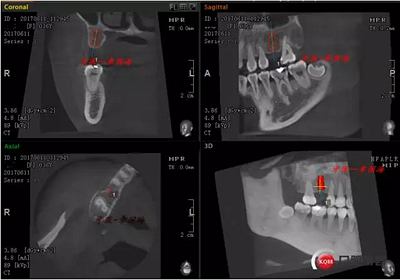

1.右上6缺失,種植修復。因空間關(guān)系選擇相應植體,ItI(士卓曼)4.1X10mm SP SLA.

CT如圖示